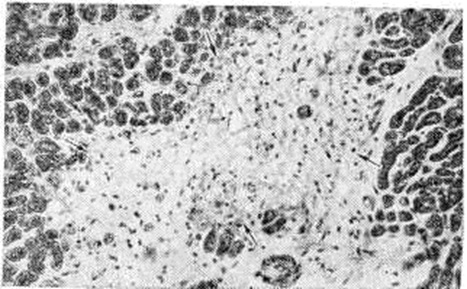

Рис. 4.

Микропрепарат миокарда при очаговом интерстициальном миокардите: между пучками волокон миокарда виден ограниченный клеточный инфильтрат (указан стрелкой); × 37.

Рис. 5.

Микропрепарат миокарда при диффузном интерстициальном миокардите: клеточный инфильтрат (указан стрелками) в межуточной ткани миокарда, раздвигающий мышечные волокна; × 200

По характеру воспалительной инфильтрации (пролиферативный компонент воспаления) при интерстициальном (межуточном) Миокардит различают очаговый и диффузный варианты. При первом варианте клетки воспалительного инфильтрата располагаются в виде более или менее крупных, но ограниченных гнёзд (рисунок 4). При втором варианте клетки воспалительного инфильтрата диффузно пронизывают межуточную ткань миокарда, раздвигая сердечные мышечные волокна (рисунок 5), располагаясь вдоль них и охватывая различные по протяжённости участки миокарда. При диффузном Миокардит не обязательно тотальное поражение, охват воспалением всей массы миокарда, что бывает при острейшем, бурно развивающемся Миокардит Большей частью воспаление, даже диффузное, имеет мозаичный характер, поражая иногда избирательно или преимущественно субэндокардиальные слои миокарда. Можно предположить, что в начале развития такого Миокардит наблюдается расстройство микроциркуляции и проницаемости в терминальном сосудистом русле. Этот период, по-видимому, не бывает длительным и сменяется нарастающими экссудативными и пролиферативными процессами в строме миокарда.